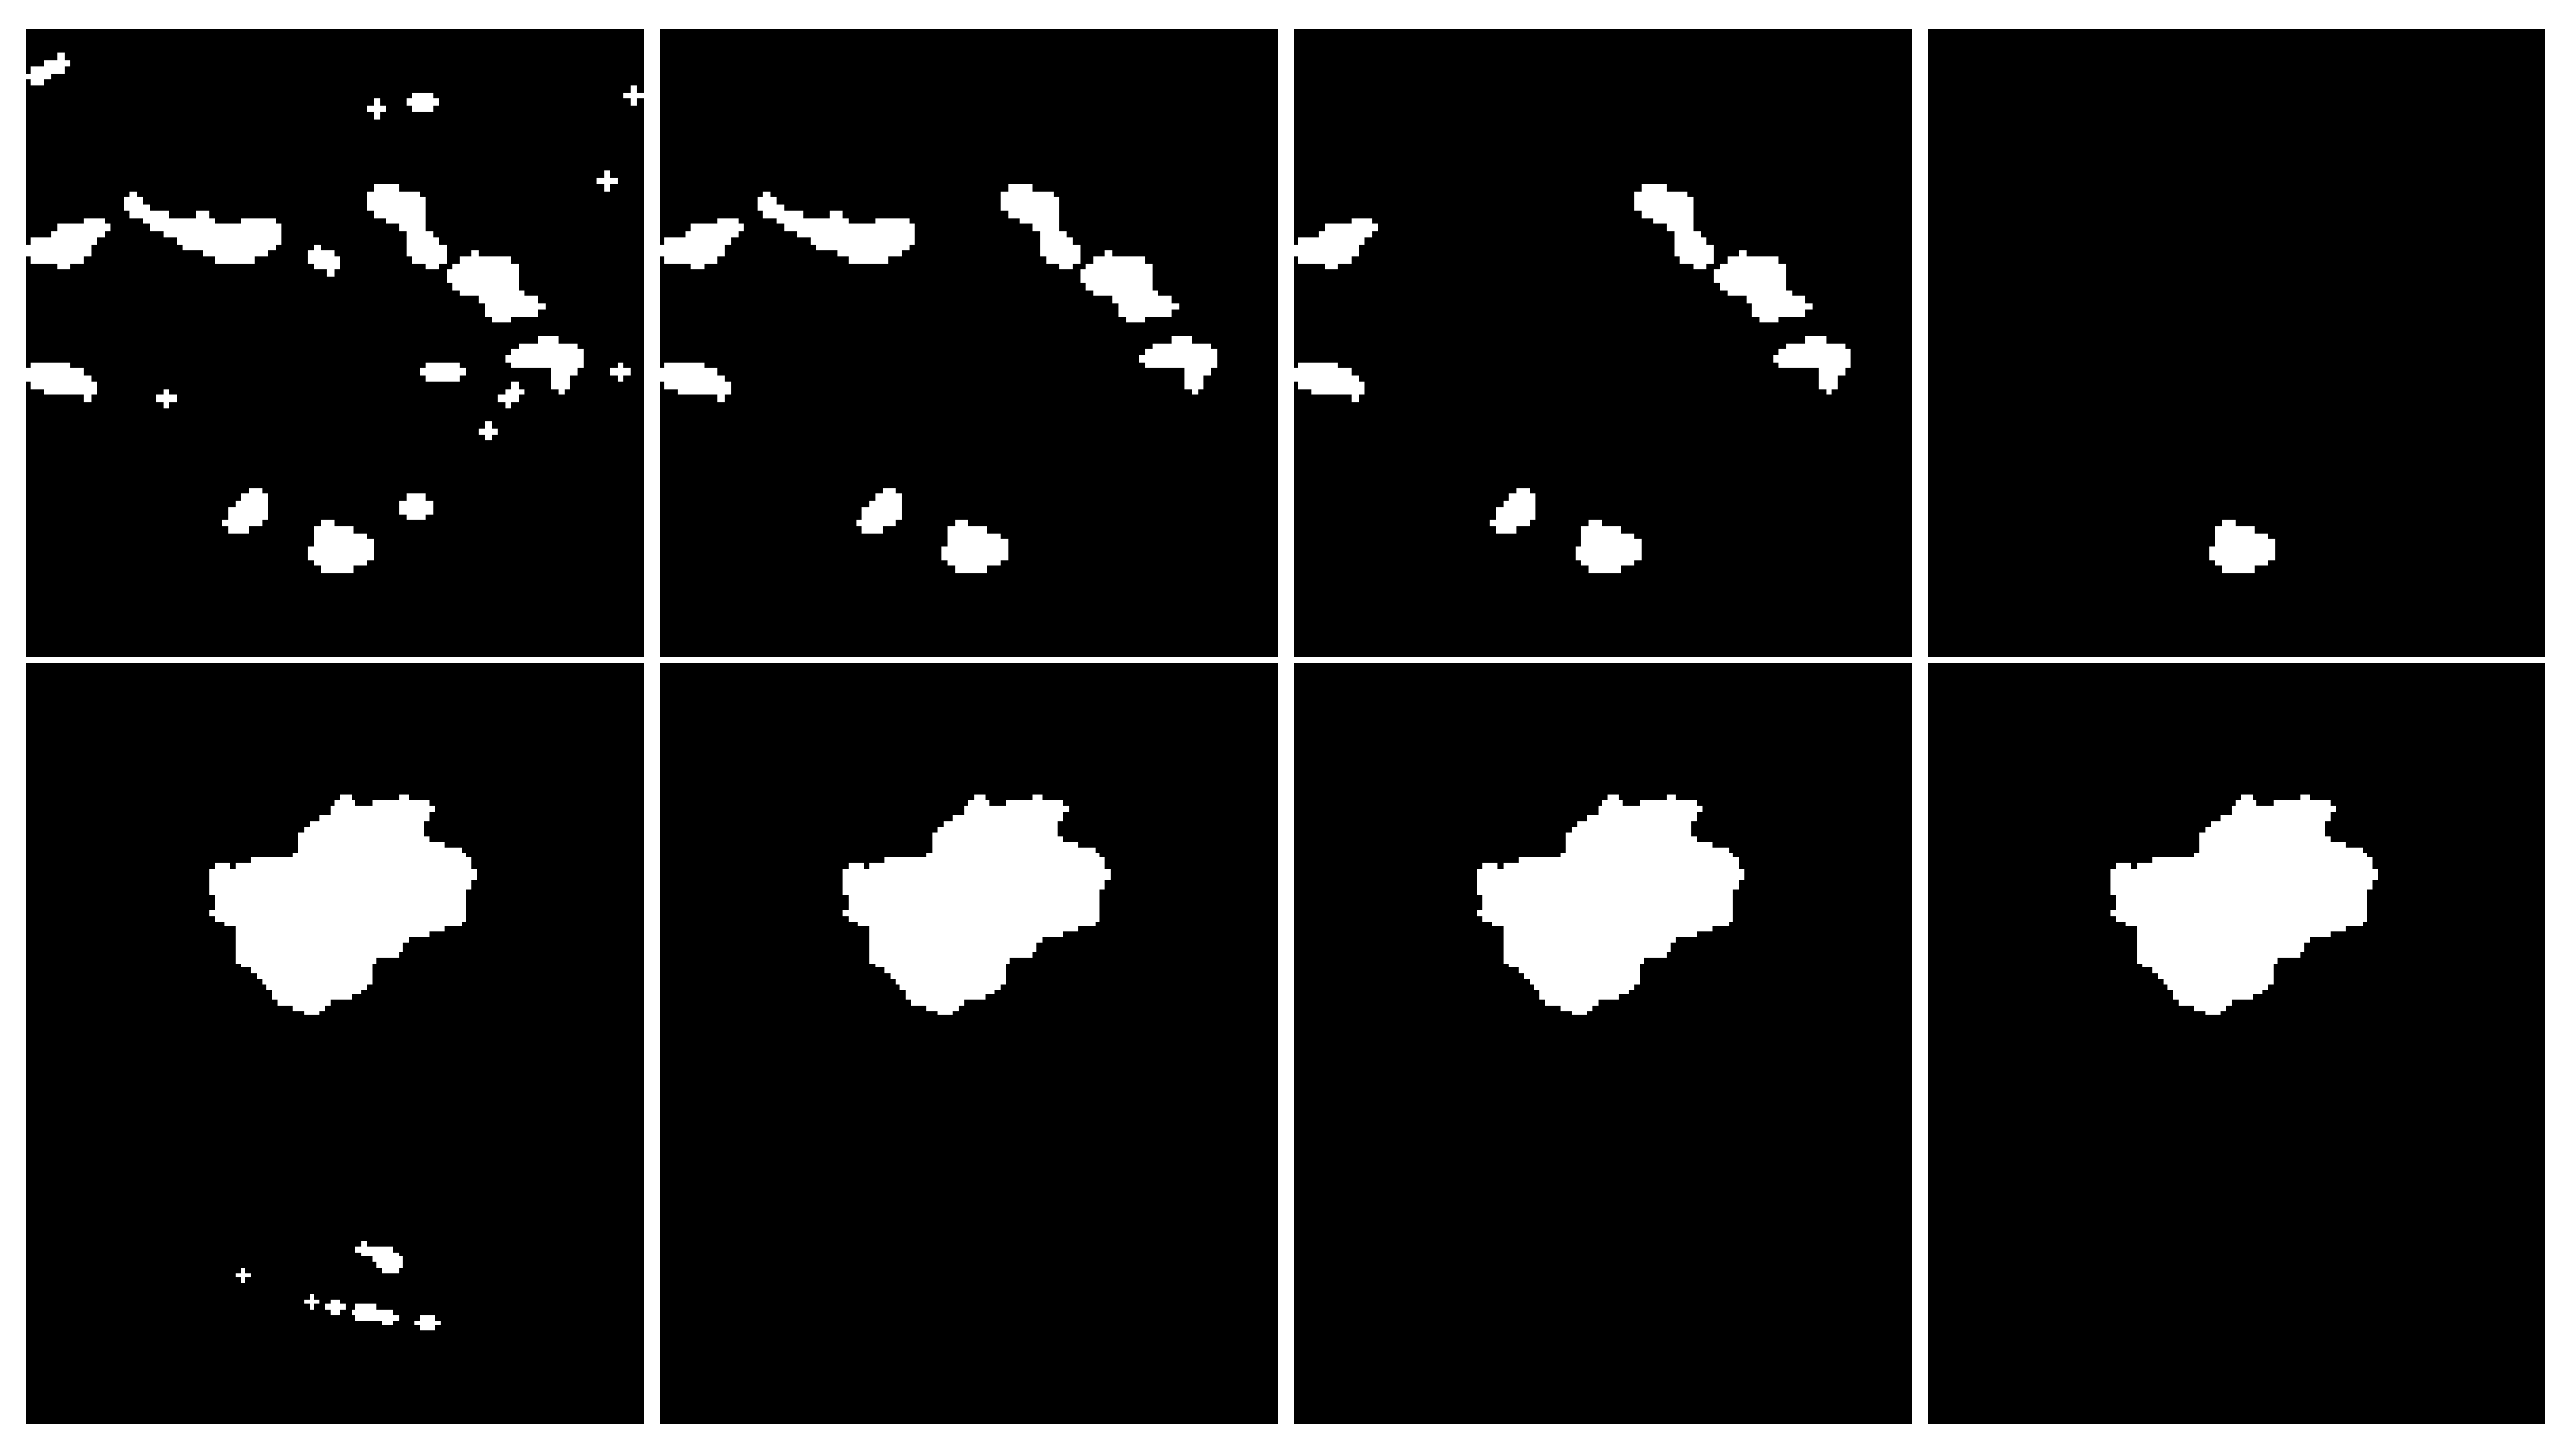

- post-processing: performed to refine the segmentation and to properly identify the ROI from each binary mask obtained in the previous step;

3.2.4. Post-Processing